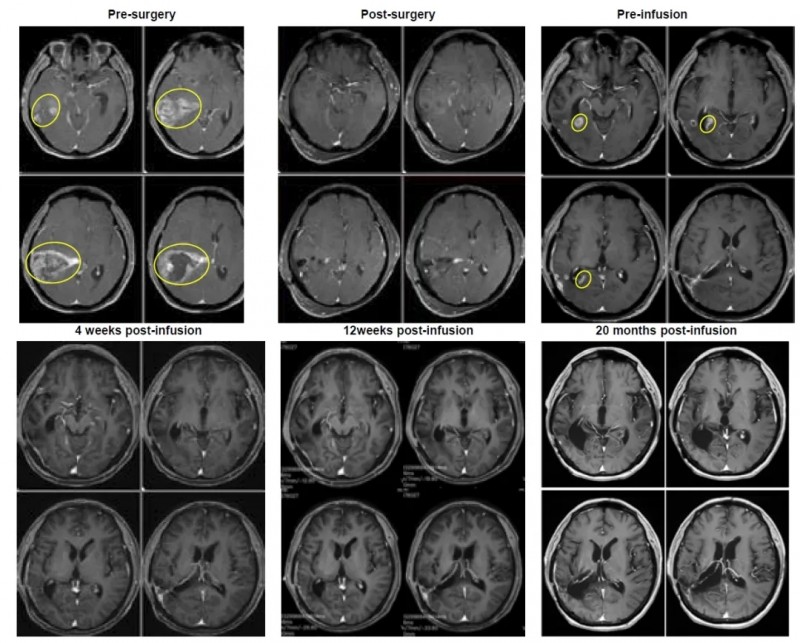

结果显示:输注前患者复发病灶最大直径达2.8cm,而输注后4周(2024年1月8日),肿瘤被完全切除;截至2025年9月9日,患者已维持完全缓解状态超过1.8年,持续获益显著(详见下图)。

▼该患者治疗过程中的磁共振成像(MRI)图像。

▲图源“BMJ”,版权归原作者所有,如无意中侵犯了知识产权,请联系我们删除

综上,该研究证实,即便胶质母细胞瘤被归类为“冷肿瘤”,其肿瘤浸润淋巴细胞仍可在体外有效扩增;而颅内病灶的完全缓解,更直接证明了TIL细胞具备穿过血脑屏障的关键能力——这一突破解决了脑瘤治疗的核心难题之一。从CAR-T到TIL疗法,免疫治疗正持续突破脑癌治疗的“禁区”,为晚期脑瘤患者带来了新的希望和选择!更重要的是,从患者早期手术切除组织中提取的TIL细胞,成功实现了复发性肿瘤的缓解,这凸显了早期留存肿瘤组织标本,对复发性GB患者后续接受TIL治疗的重要临床价值。